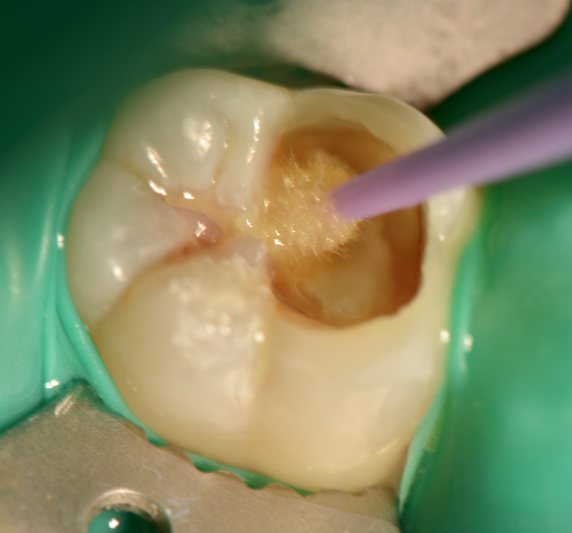

A female patient presented with sensitivity and occasional pain on stimulus in her lower left back tooth. On clinical examination deep carious lesion was present in her lower left first molar tooth (Fig.1). Tooth was non tender to percussion. Radiographic examination revealed deep lesion in close proximity to the pulp with no significant periapical changes (Fig. 2). Patient had a high caries index and therefore a bioactive restoration with Predicta Bulk was considered.

Fig. 1. Deep carious lesion in lower left first molar

Fig. 3. Excavation with polymer bur

Fig. 4. Carious lesion after initial excavation